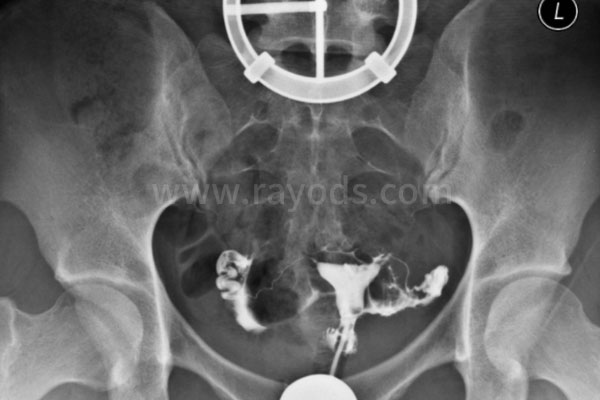

我做试管婴儿的第一个阶段是做检查,记得当时和老公一起去的。他的检查项目比较简单,好像就是查了下精液和血液。我的就比较多了,有肝功能、肾功能,一串细菌,尿常规还有各种性激素检查,总之就是一大堆。这里提醒大家子宫输卵管造影要在月经干净后一周内进行。

检查完就开始定方案了,因为我的检查结果不是很理想,医生给我选择了长方案。这个方案说白了就是要打很多针,同时要花时间调养好身体,让身体各方面的指标为下一步做好准备。我在月经第21天后开始打降调药物,好像打的是菲林。降调过后又要打促排针,当时我做了两次B超观察卵泡情况,第一次时卵泡几乎没什么变化。好在后面药物起作用了,第二次B超后,我就开始打夜针准备取卵了。